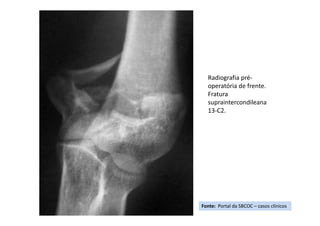

Fonte: Portal da SBCOC – casos clínicos

Radiografia pré-

operatória de frente.

Fratura

supraintercondileana

13-C2.